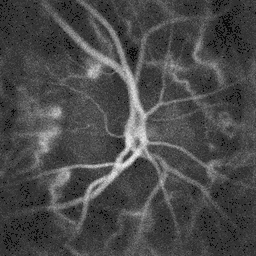

Blood flow in the retina and choroid in the optic disc region can be revealed non invasively by near-infrared laser Doppler imaging.[4] Laser Doppler imaging can enable mapping of the local arterial resistivity index, and the possibility to perform unambiguous identification of retinal arteries and veins on the basis of their systole-diastole variations, and reveal ocular hemodynamics in human eyes.[5] Furthermore, the Doppler spectrum asymmetry reveals the local direction of blood flow with respect to the optical axis. This directional information is overlaid on standard grayscale blood flow images to depict flow in the central artery and vein.[6]

Blood flow in the optic disc revealed by holographic laser Doppler imaging.[4] -